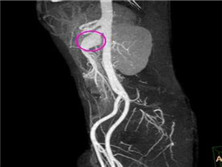

肠系膜动脉瘤

肠道动脉瘤(mesentericaneurysm)可分为肠系膜上动脉主干、分支动...